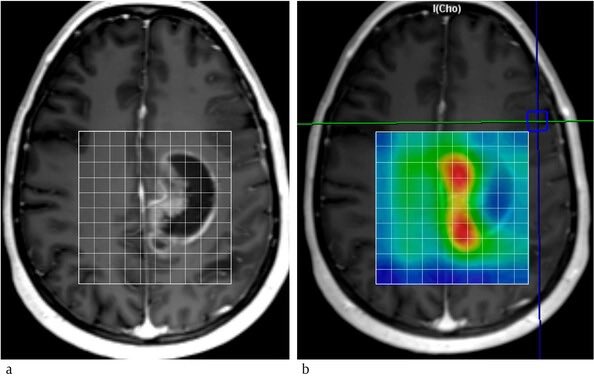

E.g. look at the scan below, on T1+C image, one can’t say what is the active growing part of the mass.

But multi-voxel MRS for Choline reveals red areas with ⬆️choline=indicating rapid proliferation.

T1 hypo intense area is probably the least proliferative, necrotic part.